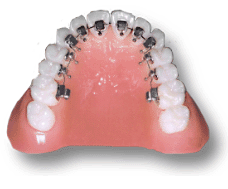

メタルブラケット

何といっても一番しっかりしている。装置費用も割安。審美的には△。